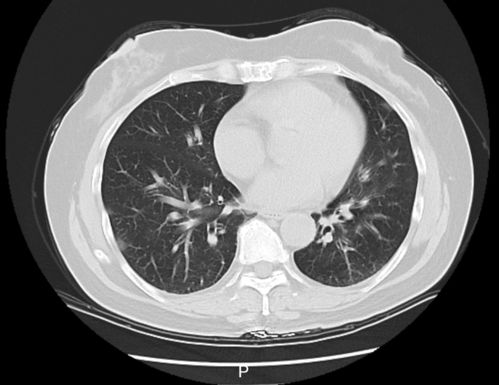

男子甲流后患病毒性肺炎四肢末端花斑:冬季流感高发期的警示 本文通过一个真实案例,详细介绍了甲流的严重性和预防措施,呼吁大家重视冬季呼吸道疾病的防护。 微博热点 2025年01月06日 23:25 0 点赞 0 评论 285 浏览